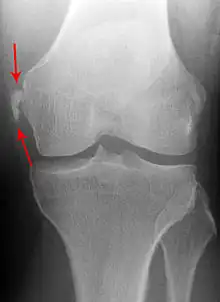

| Pellegrini-Stieda syndrome. Also visible is a fracture of the patella. |

Pellegrini–Stieda syndrome (also called Stieda disease and Köhler–Pellegrini–Stieda disease) refers to the ossification of the superior part of the medial collateral ligament of the knee. It is a common incidental finding on knee radiographs. It is named for the Italian surgeon A. Pellegrini (b. 1877) and the German surgeon A. Stieda (1869–1945).[1] While the eponym is credited to Pellegrini and Stieda, the condition was first discovered by Köhler in 1903, before any namesakes. Pellegrini-Stieda combines the aforementioned radiographic findings and concomitant medial knee joint pain or restricted range of motion.[2]

Diagnosis is typically made on radiographs demonstrating the Pellegrini-Stieda syndrome sign accompanied by pain or restriction of range-of-motion of the knee joint.[2] Pellegrini-Stieda syndrome sign is typically described by a longitudinally linear opacity, which is a process that is describes characteristic of calcification in the soft tissue located medial to the medial femoral condyle.[2] This calcification seen on imaging represents the ossification of the medial collateral ligament, which typically does not develop until approximately three weeks after the initial injury.[2]It is important to note to distinguish this radiographic finding from that of a medial femoral condyle avulsion fracture, which is an injury in which a pulling force of a tendon or ligament fractures away a piece of the bone from its attachment site.[2]